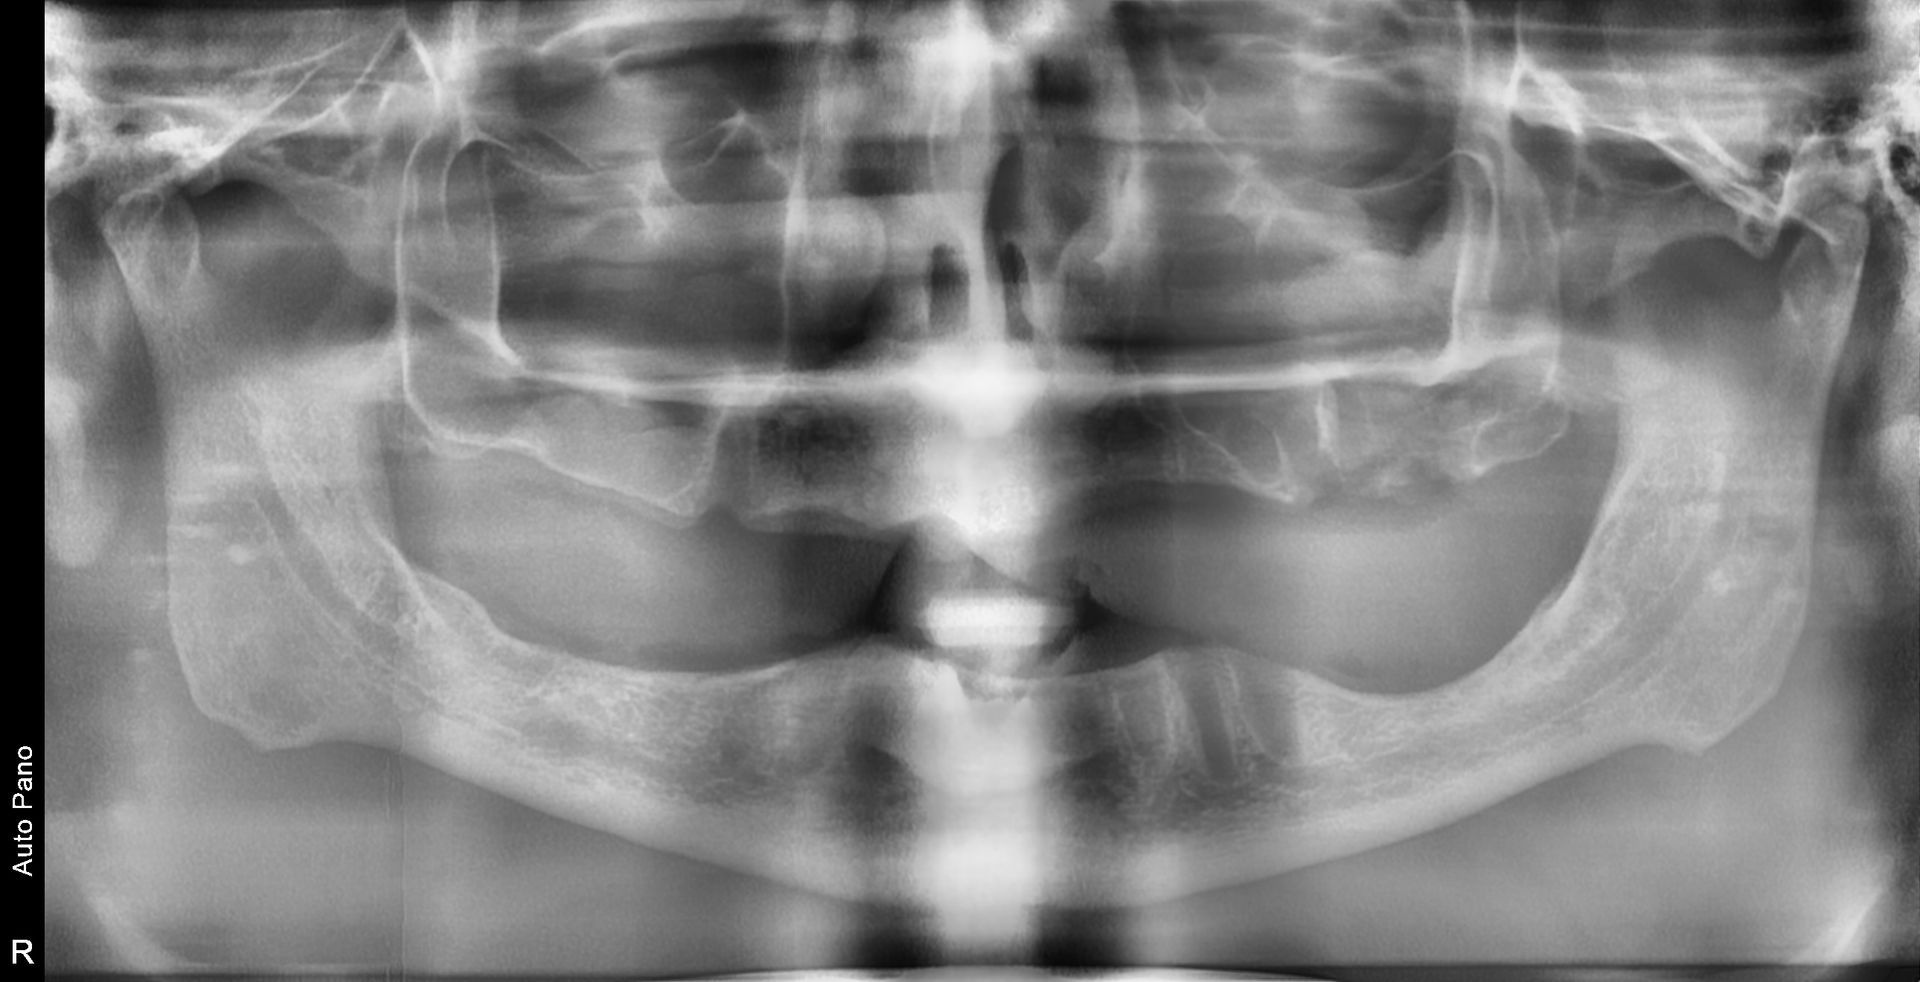

The panoramic radiograph confirmed a fully edentulous state in both the maxilla and mandible,

with all teeth already extracted.